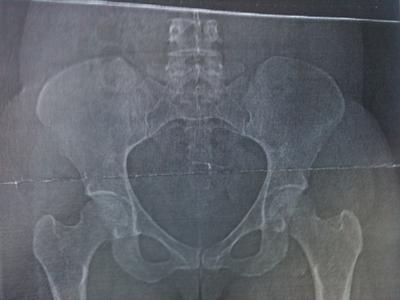

Fortunately you don't hip have hip dysplasia. The sockets, acetabulum, are normally formed and roofed, and the hips sit nicely in the sockets.

Your xray. Like I said too small, but I think I see small cam and pincer deformities of Femoro acetabular impingement syndrome in both hips.

Both may progress to osteoarthritis of the hip and I think on the hip on the reading left there may be some thinning of the cartilage.

You have really quite mild Femoro Acetabular Impingement syndrome and very early osteoarthritis in one of the hips. I can't tell which from the X-ray as they aren't marked. Hence your radiologist had little to say.